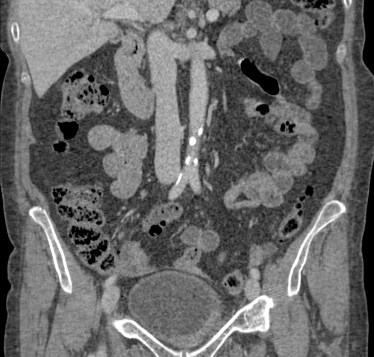

SEGUIMIENTO:

Los pacientes con cáncer de vejiga no músculo invasivo tiene alto riesgo de recidiva y progresión de la enfermedad, por tanto deben ser vigilados mediante cistoscopia, citología y estudios de vías superiores cada 1 – 2 años en ausencia de recurrencia. Los pacientes tratados de cáncer invasivo requieren pruebas inclusive con mayor frecuencia tras la cistectomía, ya que el objetivo es buscar metástasis no conocidas que pueden ocurrir en ausencia de síntomas.

Las metástasis afectan el hígado, pulmones, glándulas adrenales, hueso, bazo, riñones y más raramente el peritoneo. Tumores metacrónicos del tracto superior se dan hasta en el 2-6% de las ocasiones. Una uro-Tc nos sirve para valorar al mismo tiempo la enfermdad metastásica y los tumores metacrónicos del tracto superior en los pacientes de cistectomizados de alto riespo.

Tras el tratamiento de la recidiva y nefrostomía para la hidroureteronefrosis, vuelve acudir al hospital a los 9 meses por episodio de dolor en FD y malestar general. Se realiza una ecografía de urgencias.

Se realiza nueva TC bifásico abdominopélvio y Uro TC.

- Paciente con numerosas recidivas por Cá vejiga.

- Ha desarrollado un tumor metacrónico en pelvis renal derecha, también responsable de la hidroureteronefrosis.

- Mala evolución radiológica del proceso a expensas de metástasis pulmonares y hepáticas.